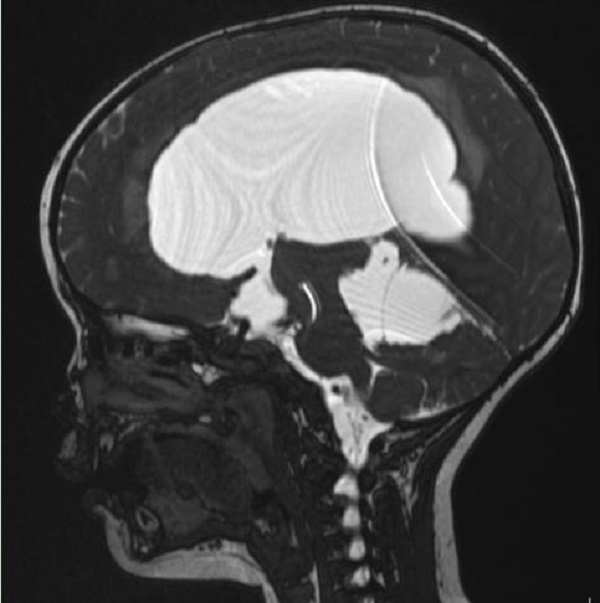

一岁多的赫赫小朋友自出生头颅就比同龄小孩大,近半月来进食后出现呕吐,伴头痛,在当地医院及省内多家医院治疗不见好转,于是来到陕健医二一五医院神经重症监护室,因患儿近半月多不能正常进食,入院时精神萎靡,头颅MRI检查提示“脑室系统扩大,双侧脑室额角周围间质水肿,左侧丘脑占位病变,鞍上池及小脑上池扩大”。

为进一步鉴别脑积水类型,行磁共振3D FIESTA序列检查可见侧脑室扩大明显,中脑导水管中段阻塞、三脑室底受压下陷,诊断梗阻性脑积水。